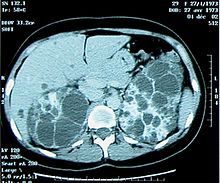

Bilan d’insuffisance rénale chronique: que voit-on?

Multiples kystes et gros rein: probable polykystose rénale

Qu’est ce que c’est?

polykystose rénale